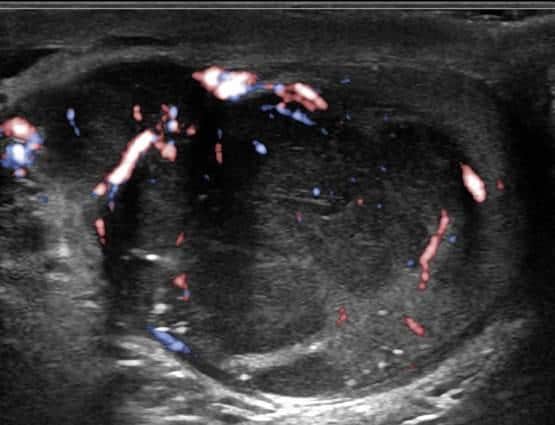

U tinh hoàn

» Thông tin: Nam giới – 28 tuổi.

» Lâm sàng: Sưng tinh hoàn.

# U tinh bào (Seminoma).